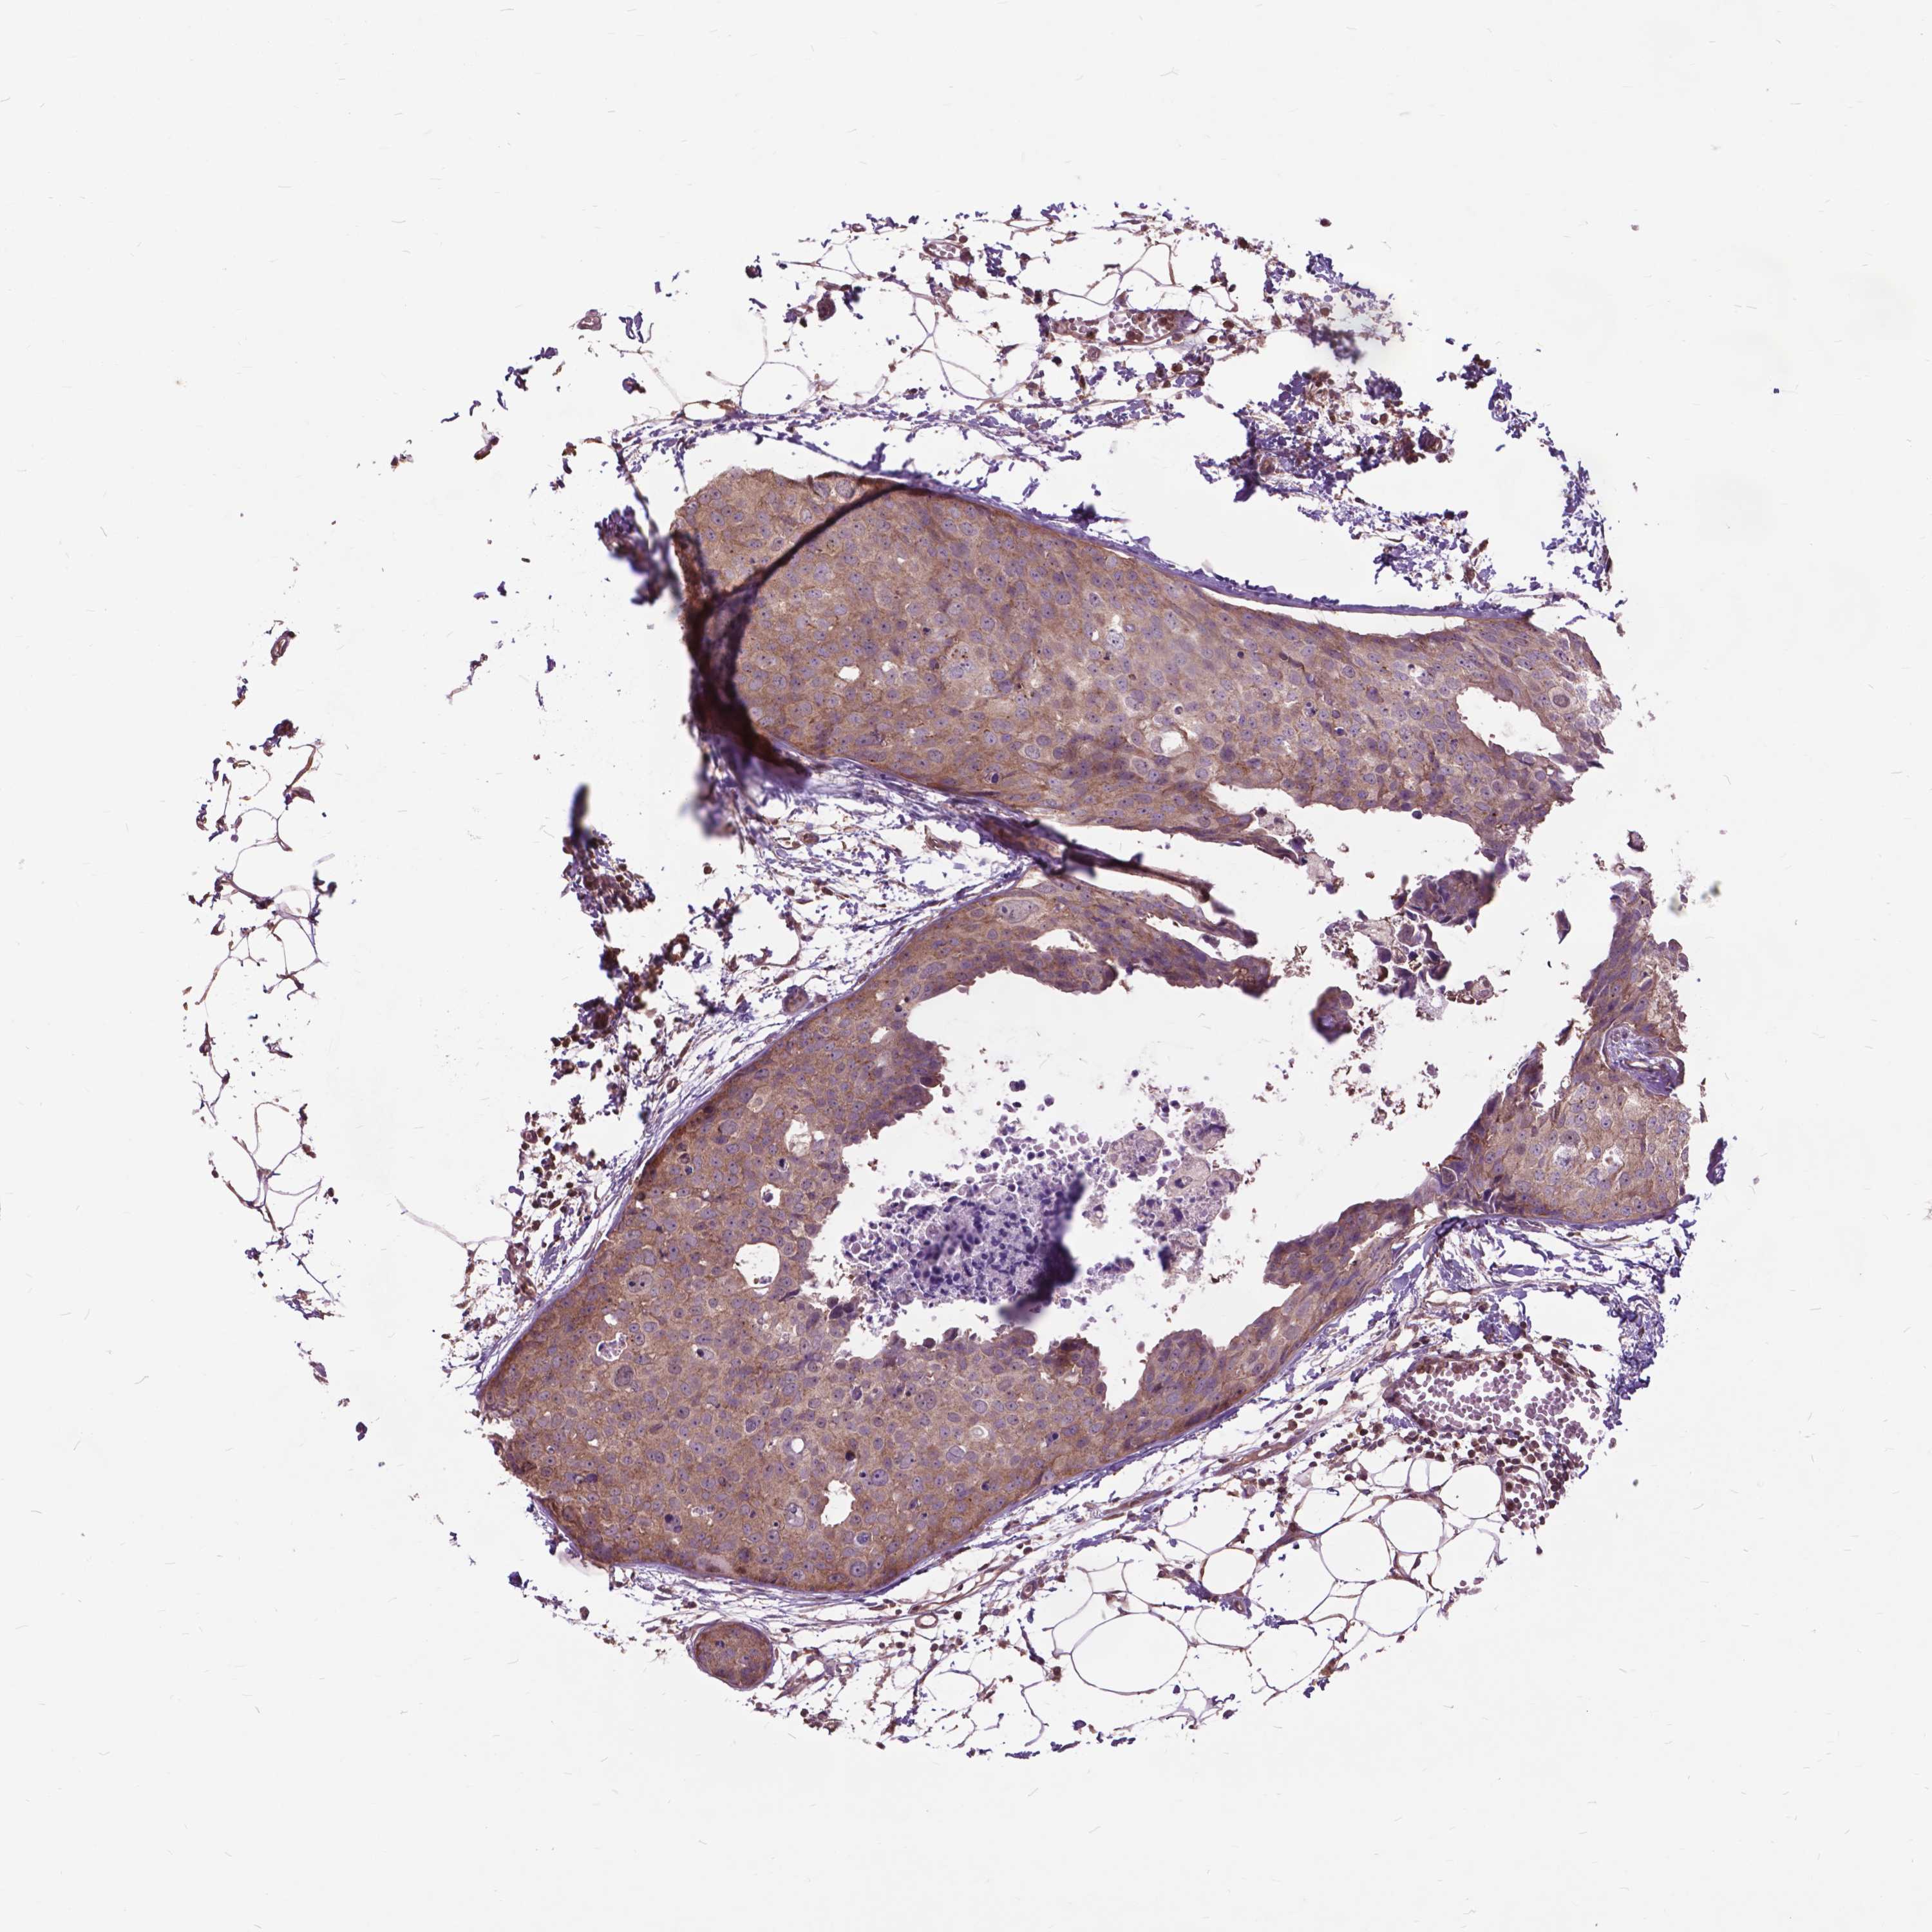

BRCA TCGA BRCA VALIDATION PROTEIN EXPRESSION

ANTIBODIES

AND

VALIDATION